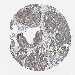

PANCREATIC CANCER - Protein expressioni

A mouse-over function shows sample information and annotation data. Click on an image to view it in a full screen mode. Samples can be filtered based on level of antibody staining by selecting one or several of the following categories: high, medium, low and not detected. The assay and annotation is described here.

Note that samples used for immunohistochemistry by the Human Protein Atlas do not correspond to samples in the TCGA dataset.

Antibody stainingi

Antibody staining in the annotated cell types in the current human tissue is reported as not detected, low, medium, or high, based on conventional immunohistochemistry profiling in selected tissues. This score is based on the combination of the staining intensity and fraction of stained cells.

Each image is clickable and will lead to virtual microscopy that enables deeper exploration of all samples and also displays staining intensity scores, fraction scores and subcellular localization as well as patient and tissue information for each sample.

Antibody HPA010645

Antibody HPA017055

Antibody HPA046639

Staining

High

Medium

Low

Not detected

Intensity

Strong

Moderate

Weak

Negative

Quantity

>75%

75%-25%

<25%

None

Location

Nuclear

Cytoplasmic/membranous

Cytoplasmic/membranous,nuclear

Adenocarcinoma, NOS

Adenocarcinoma, metastatic, NOS